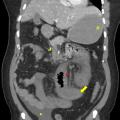

Thrombose porte et ischémie mésentérique veineuses

La thrombose de la veine porte (TVP) se caractérise par l’obstruction, le plus souvent par un thrombus, de la veine porte et/ou de ses branches portales (droite et/ou gauche). Cette obstruction peut être partielle ou complète, récente (moins de six mois) ou chronique (plus de six mois) et peut également affecter les vaisseaux…